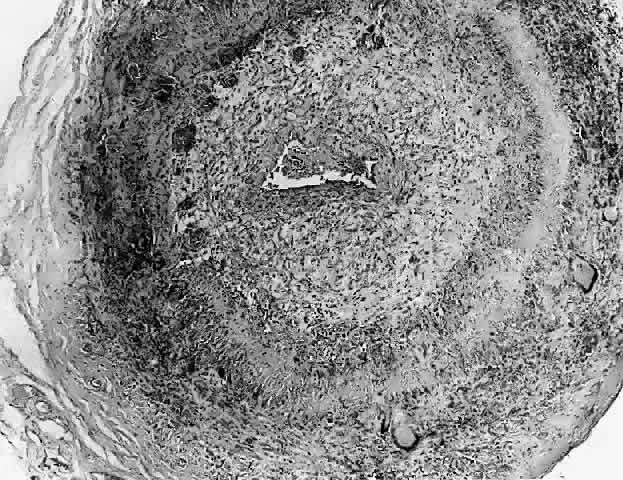

NODULAR FASCIITIS

Nodular or pseudosarcomatous fasciitis, while not usually considered part of the spectrum of idiopathic orbital inflammation, represents a localized inflammatory disease of idiopathic origin. It appears to be a reactive process involving a proliferation of immature connective tissue elements along with acute and chronic inflammatory foci (Fig. 7).102–106 This entity has been reported periorbitally in the eyelid as well as in the epibulbar tissue. It may also occur in the anterior or deep orbit. It appears as a rapidly growing mass arising over several weeks or months. It may or may not be associated with pain. At surgery, the lesion appears fairly well demarcated and slightly reddish.

Histopathology

Microscopically there is a proliferation of immature and active-appearing fibroblasts within the orbital fascial planes.102–106 These fibroblasts may be loosely connected with occasional myxoid foci interposed. Slits often appear between the fibroblasts, which appear to be quite plump and have basophilic cytoplasm. There may be rare mitoses among these cells. Only a minimal amount of collagen deposition is present. The appearance of a gradient from immature fibroblastic elements to more mature fibroblasts is characteristic of this lesion. Also associated with this process is acute and chronic inflammatory cells, capillary and endothelial cell proliferation, and occasional giant cells. Occasionally elements of this inflammatory process can be seen to invade surrounding muscle fibers and orbital fat. The proliferating capillaries are friable and bleed. When this occurs, hemosiderin-laden macrophages can be identified in the tissue. Electron microscopic evaluation of the cells present in this process shows that most are myofibroblasts. These are cells containing rough endoplasmic reticulum and no basement membrane like fibroblasts but also cytoplasmic actin filaments with fusiform densities like smooth muscle cells.3